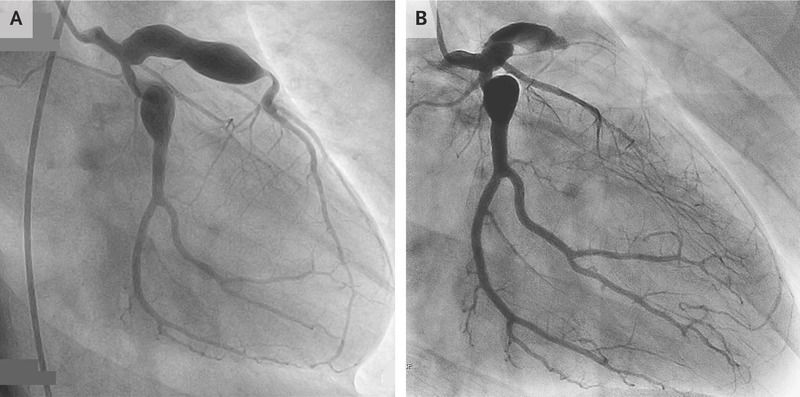

An 18-year-old man presented to the emergency department with chest pain. He had a history of Kawasaki’s disease, which had been diagnosed when he was 11 years of age. Despite treatment with intravenous immune globulin, coronary-artery aneurysms were detected on imaging (Panel A shows a coronary angiogram obtained 3 years before the current presentation). At the time of the current presentation, his medications included aspirin and warfarin. An electrocardiogram showed ST-segment elevations in leads V1 to V3. Emergency coronary angiography revealed occlusion of the left anterior descending artery (Panel B). Kawasaki’s disease is an acute, idiopathic, self-limiting vasculitis that primarily affects children. Clinical features include fever, nonexudative conjunctivitis in both eyes, mucositis, cervical lymphadenopathy, polymorphous rash, and changes in the hands and feet. Because not all these features are necessarily present and there is no specific diagnostic test for Kawasaki’s disease, the diagnosis may be missed in childhood or occur at such an early age that the adult patient has no recollection of illness. Affected children are at risk for cardiovascular complications. The patient underwent coronary-artery bypass surgery. At follow-up 3 years after presentation, he was doing well and had no further cardiac symptoms.